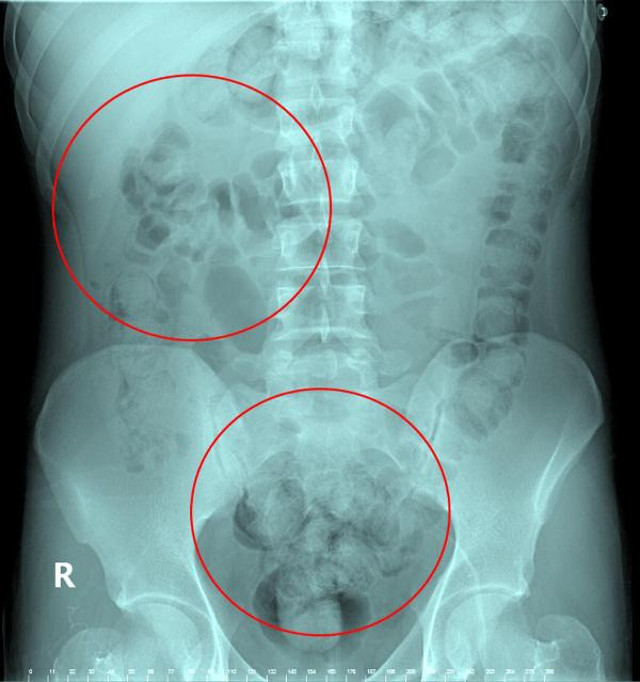

Abone olVan'dan otobüs ile Ankara'ya gelen İran uyruklu Zadeh Ahmed Narziveh, Ankara Şehirlerarası Terminal İşletmesi'nde fenalaştı. Zarziveh, çevredekilerin haber vermesiyle gelen 112 Acil Servis ekiplerinin ilk müdahalesinin ardından Ankara Şehir Hastanesi'ne kaldırıldı. Tedavi altına alınan Narziveh'in çekilen röntgen filminde midesinde cisim tespit edildi.

Ameliyata alınan Zarziveh'in midesinden 2'si patlamış 72 adet kapsül halinde uyuşturucu madde çıkarıldı. Gördükleri manzara halinde şaşkına dönen doktorlar durumu polise bildirdi. Gelen polis ekiplerinin yaptığı incelemede 890 gram uyuşturucu maddenin metamfetamin olduğu belirlendi.